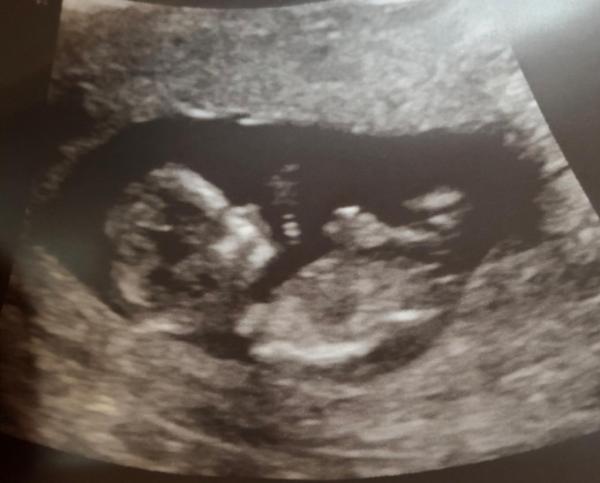

... die ersten Wochen sind nun rum... bin heute bei 12+3 und hatte mein dritten Ultraschall... bei Nr. 1 - ein Reiskorn zu sehen... bei Nr. 2 - eine Kaulquappe... war auch irgendwie süß... und heute... wow... ich glaube jetzt so langsam kommt die Freude so richtig... es ist so erstaunlich wie schnell da was in einem heran wächst und mit gerade mal 6cm schon so süß aussehen kann... wow...

Bild zu Wow... ich bin sprachlos... - Forum für April - Mamis

Wow ein sehr schönes Bild:) es sieht aus als hätte dein Krümel nen Schnuller im Mund

Es hatte kurz vorher die Hand im Mund... hat man auch ganz süß erkennen können